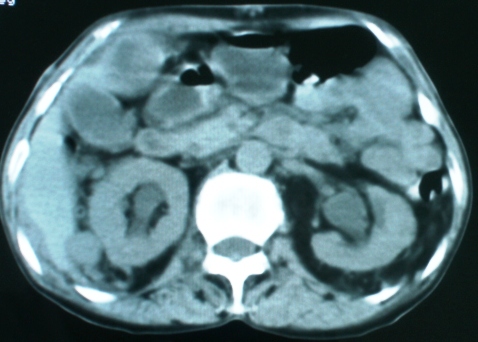

以下是引用zsl6918在2008-11-4 19:14:00的发言:[br]多发转移性改变,子宫改变不除外为原发灶